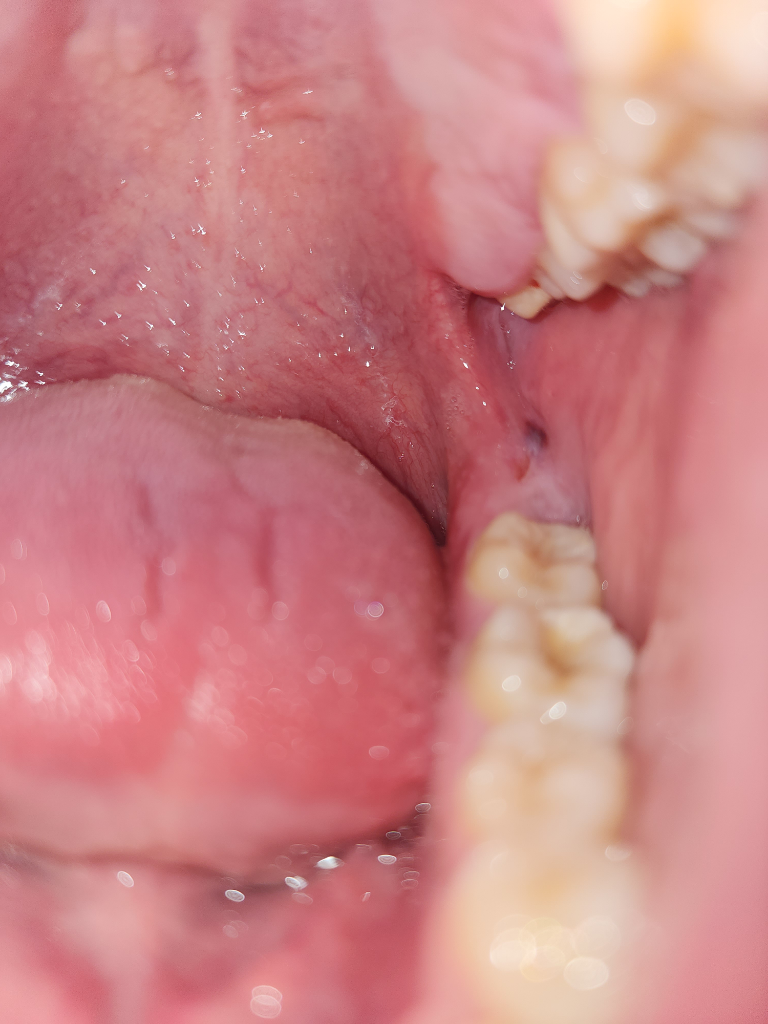

잇몸 안쪽에 상처가 났는데 피딱지 같은게 생겼습니다

밥을 먹다가 모르고 잇몸 안쪽을 씹어서 상처가 난 것

같습니다.양치를 하다가 입을 벌려서 살펴보니 상처가

난 부위에 피딱지 같은게 생겼는데 가만히 냅두면

낫나요?

• 1번 째 사진

사진상에 보이는 부위는 잇몸이 치아에 씹혀서 생긴거 같습니다. 피가 뭉쳐잇는거 같으니 터트리시면되거나 시간이 지나면 괜찮아 지실꺼에요.